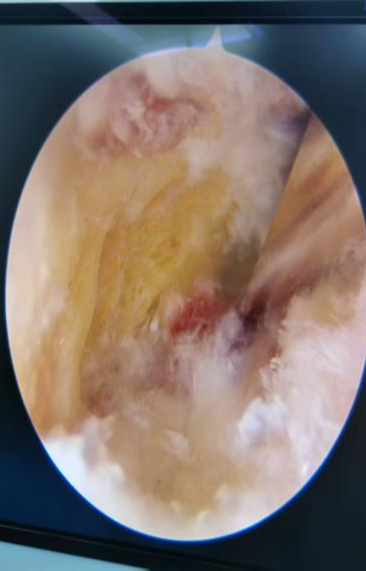

为了解决这个难题,我院足踝外科的医生们一直专研微创技术,还结合了国内外最先进的治疗经验,终于研究出了关节镜微创治疗的好方案。这个技术最大的好处就是伤口小、定位准、好得快:只需要在脚后跟骨头上开个约0.5厘米的小口,通过关节镜的高清镜头,直接找到病根。医生能清楚地看到发炎的部位,精准松解筋膜,清理掉发炎的坏组织;如果脚后跟还有骨刺,也能一起磨掉,从根儿上解决疼痛的问题。

而且手术全程出血量特别少,几乎不损伤周围正常的组织,大大降低了术后感染的风险,伤口渗液的时间也变短了,住院天数比传统手术少了一半还多。最重要的是,能很好地保护脚踝功能,让患者术后恢复得更舒服、更利索。

这次做手术的患者,被足跟痛折磨了一年多,做了6个多月的保守治疗都没效果,正常生活都受大影响了。团队专门为他定制了手术方案,术前仔细做了检查、评估了身体状况,手术过程特别顺利。术后第二天,患者就在医生护士的指导下下床慢慢活动了,足跟的刺痛感明显减轻;伤口恢复得也特别好,没有渗血渗液,没多久就顺利出院了。复查的时候,患者的足底疼痛完全消失了,能正常走路、运动。